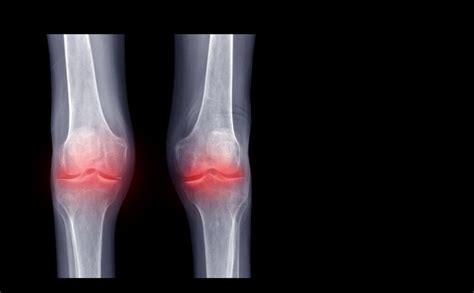

Alright, so Pseudogout , the star of our show, is a type of arthritis. Don’t worry, it’s not as scary as it sounds. Essentially, it happens when calcium pyrophosphate dihydrate (CPPD) crystals form in your joints. Think of these crystals as tiny, sharp needles that get lodged in the joint. These crystals then trigger inflammation, leading to sudden and painful attacks. Common symptoms include intense joint pain, swelling, and warmth in the affected area. The pain can come on quickly and be pretty severe, often mimicking the symptoms of gout (hence the name “pseudogout,” meaning “false gout”). Usually the knee is the main location, but it can also affect other joints like the wrist, ankle, elbow, shoulder, and even the small joints of the hand and feet. The episodes of pseudogout can last for days or even weeks. It’s crucial to seek medical attention if you suspect you have pseudogout, as proper diagnosis and treatment are essential for managing the symptoms and preventing long-term joint damage. Early diagnosis and treatment can significantly improve your quality of life, allowing you to get back to enjoying your day-to-day activities.